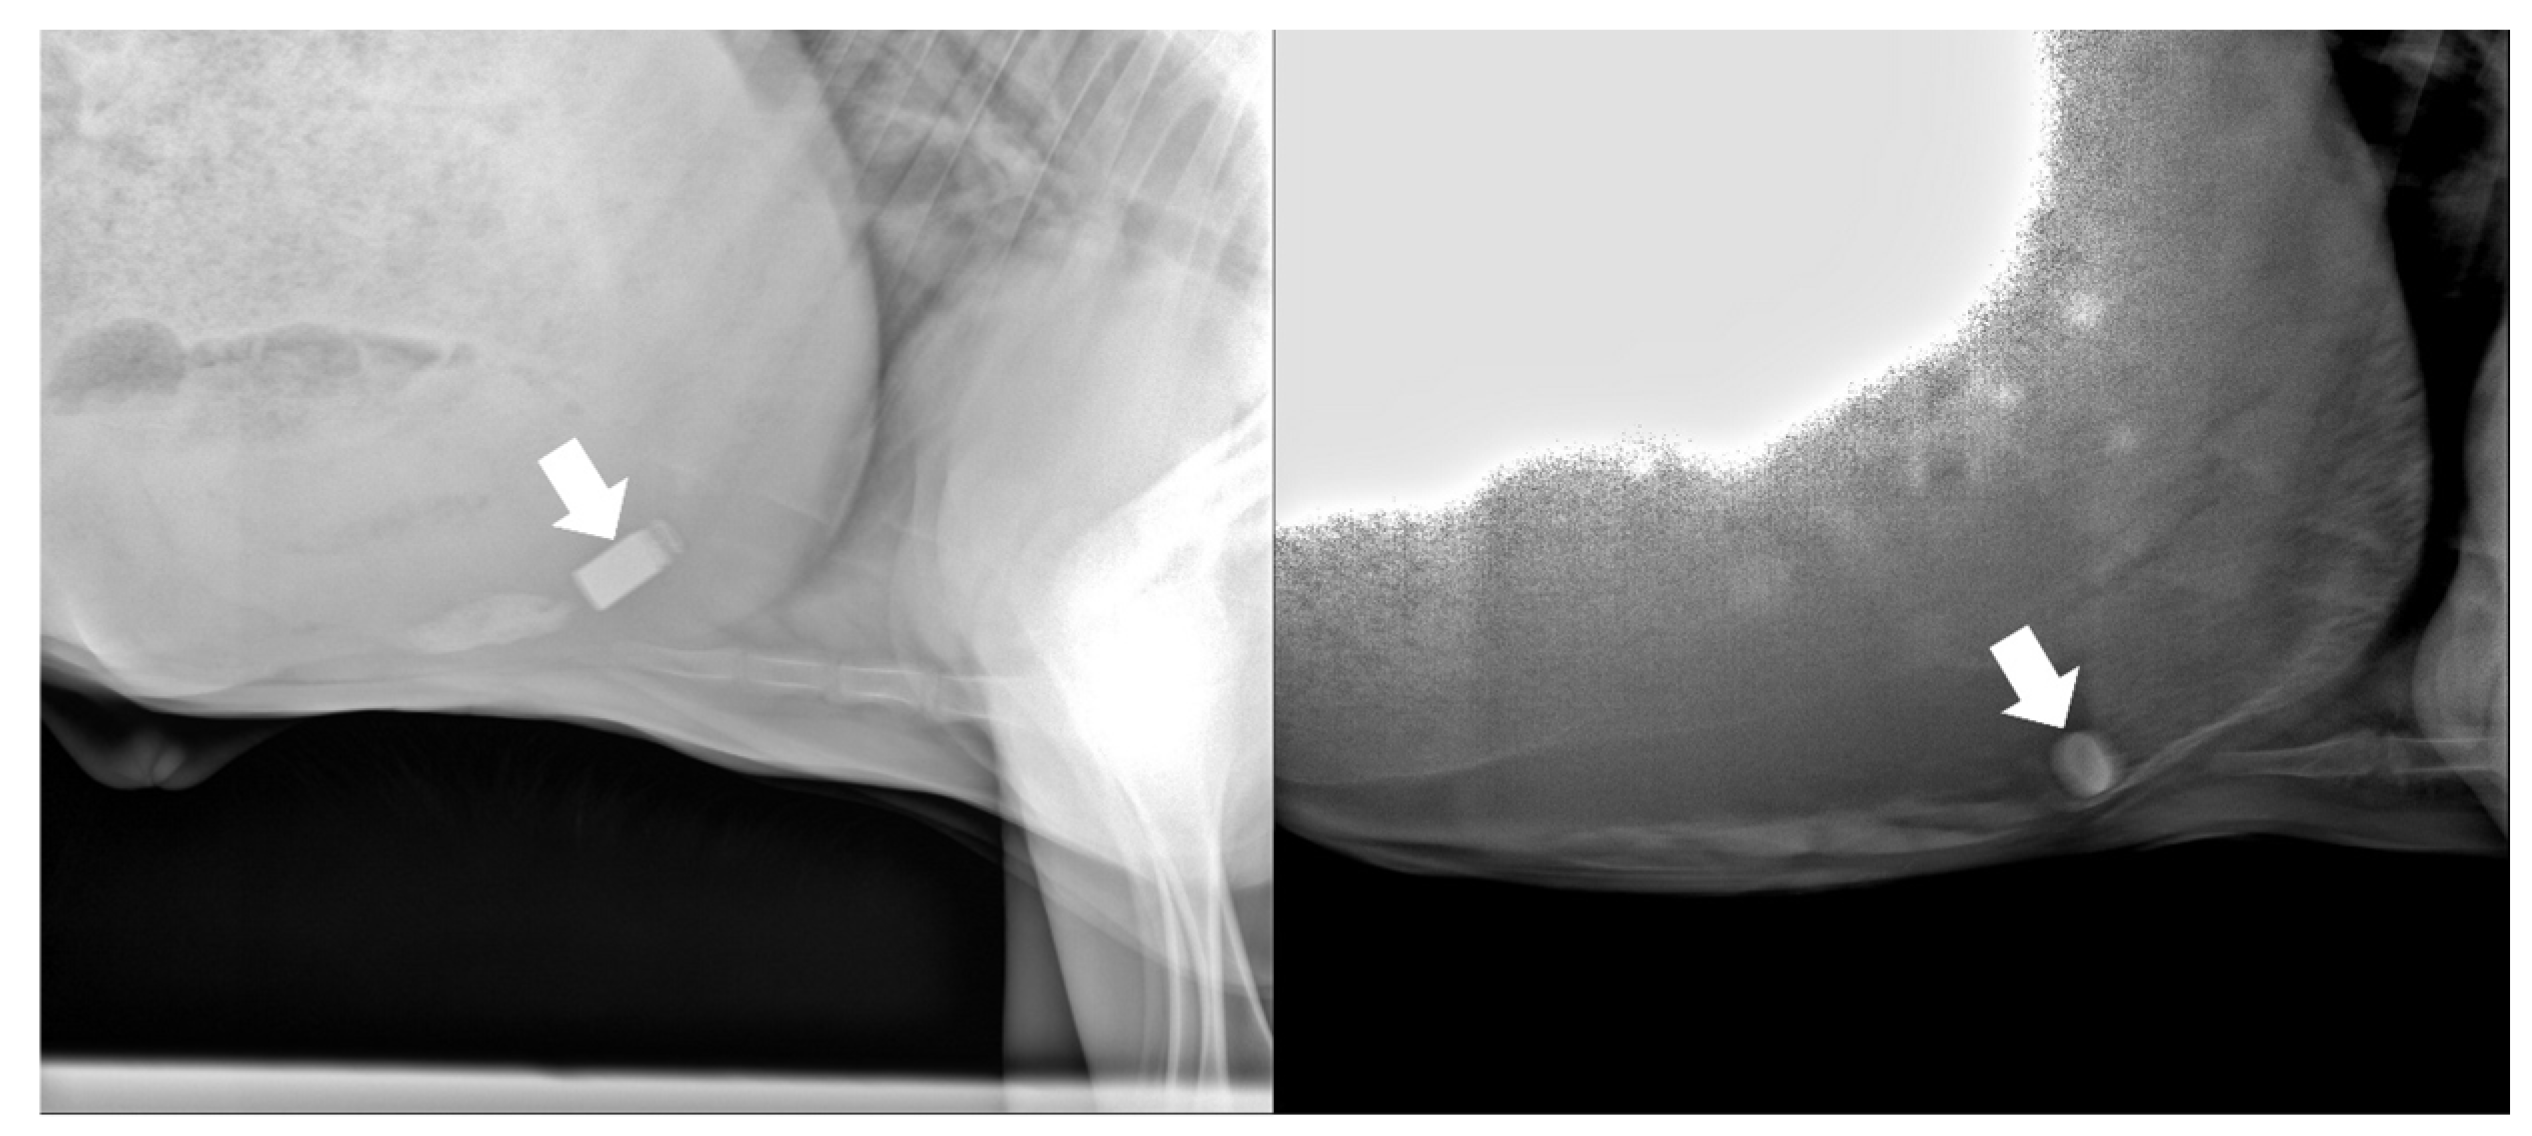

3.1. Retention and Location of the Biosensor